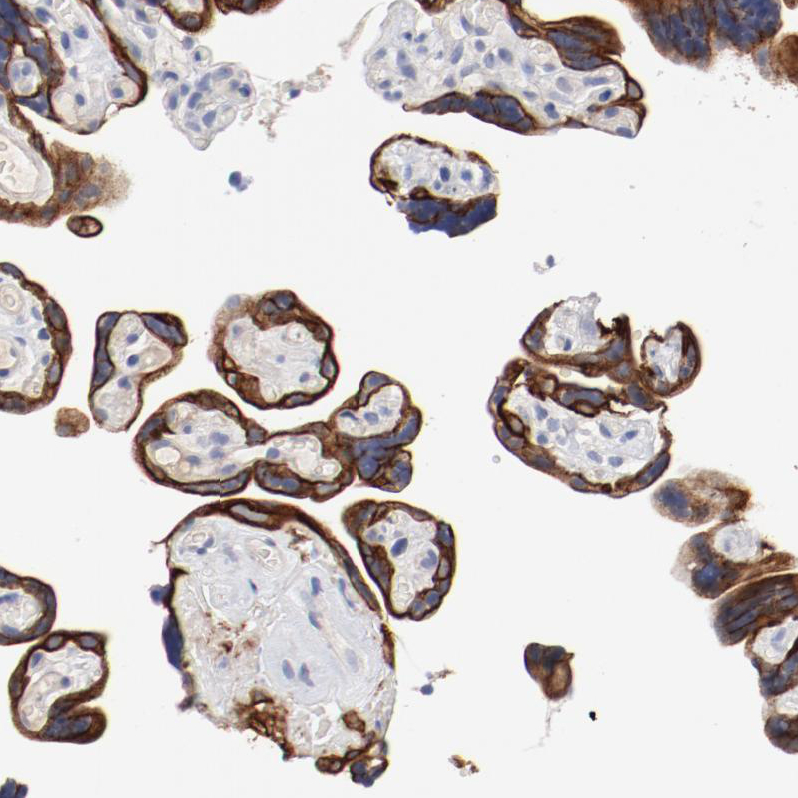

Immunohistochemical staining of human fallopian tube shows strong membranous positivity in glandular cells.